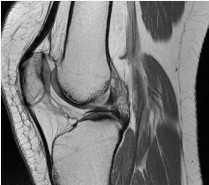

Diagnostic arthroscopy revealed similar chondral softening as was seen in the left knee. Unlike the left, the right knee exhibited mild trochlear dysplasia and an ACL with an anomalous insertion onto the anterior horn of the lateral meniscus (Figure 1, 2).

Examining and probing of this anomalous structure revealed no ACL or meniscal insertions onto the underlying tibia, and a completely mobile anterior horn of the lateral meniscus as it relates to tibial motion. In addition, there was no scarring or fibrosis to suggest a posttraumatic etiology. Nevertheless, she had no evidence of ACL insufficiency or instability, so nothing was done to the anomalous structure. We returned to the patello femoral portion of the procedure that was completed without incident, in a similar manner to the left knee.

Figure 1: Arthroscopic image of the anomalous insertion of the anterior cruciate ligament on the lateral meniscus.